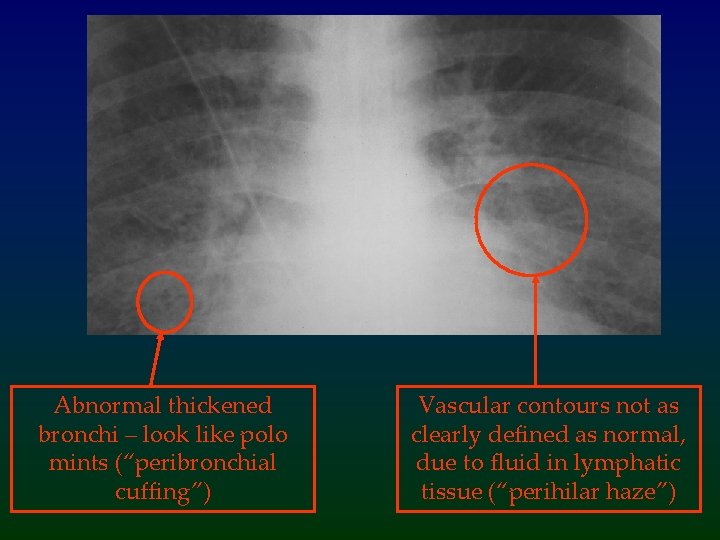

Sequence of Pulmonary Oedema 1 • The first part of the lung to become involved is the interstitial space. – Fluid first builds up in the lymphatic spaces and in the bronchial walls – These structures are normally not large enough to be visible on a CXR, but in pulmonary oedema, the fluid accumulation is so great they can be seen. At this stage, the normal sharp margin of the central vascular structures is lost, and thickened bronchial walls can be seen

Abnormal thickened bronchi – look like polo mints (“peribronchial cuffing”) Vascular contours not as clearly defined as normal, due to fluid in lymphatic tissue (“perihilar haze”)